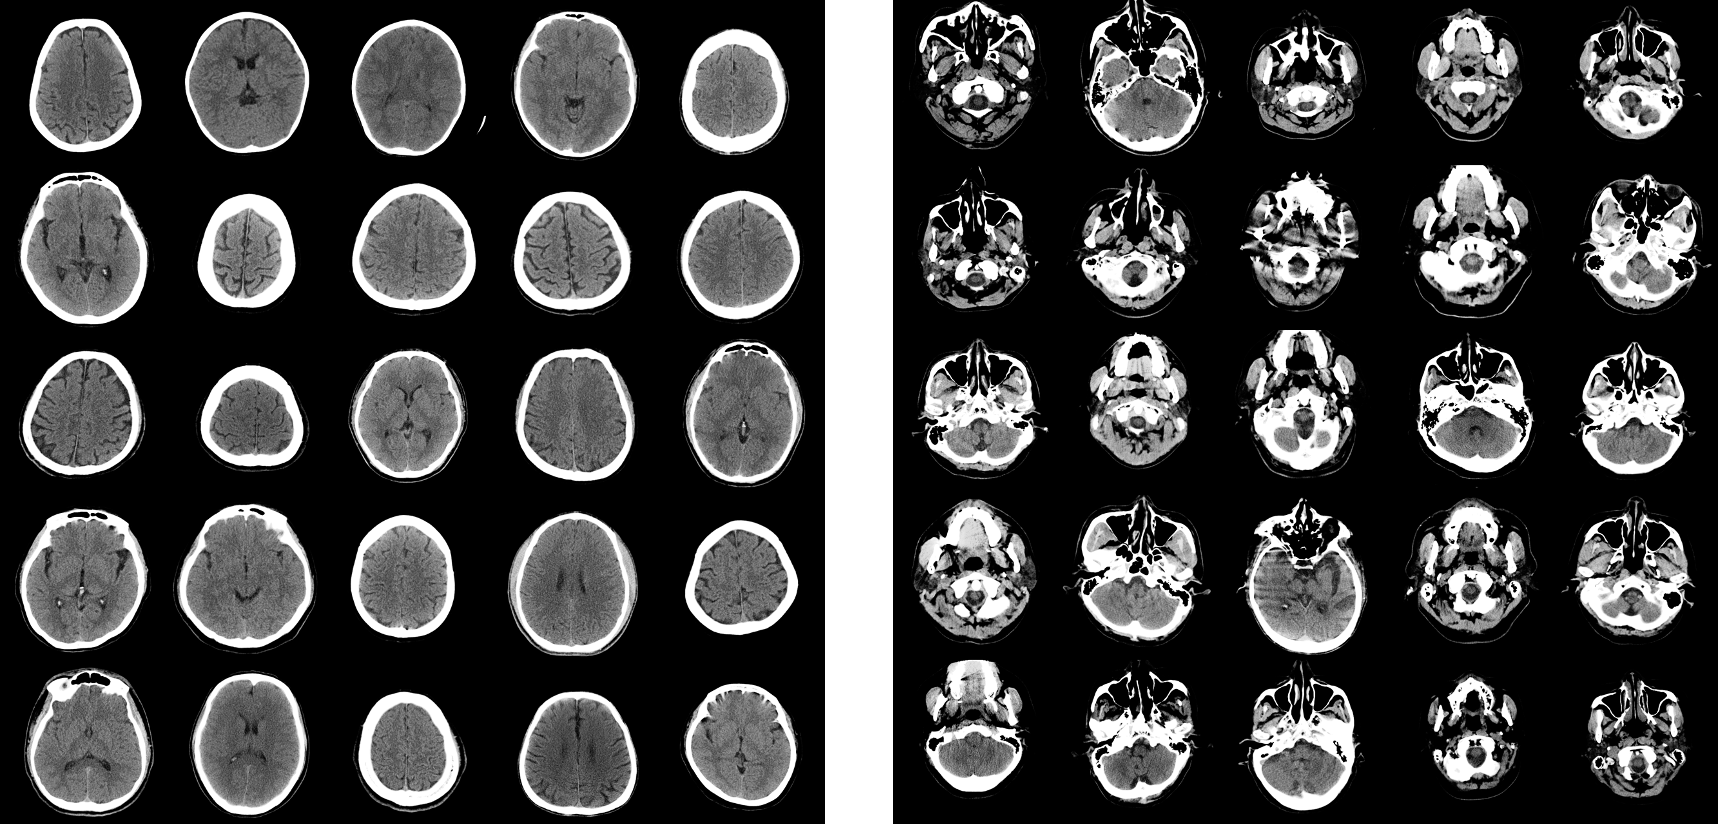

We experimented 2 schemes: (1) Calculating precision, recall, density and coverage (PRDC), and fidelity, diversity using barcode between real and synthetic images. (2) One licensed medical doctor manually split 1,000 images containing the superior part and 1,000 images containing the inferior part of the brain in real brain CT images. Criteria of splitting superior and inferior brain CT images was eye level, implying superior part of the brain CT was above the eyes, and inferior part of the brain was below the eyes. We call superior to the eye as supratentorial and inferior to the eye as infratentorial. In almost all cases, supratentorial images contain skull and brain parenchyma, however infratentorial images contain maxilla, mandible. Example images of supratentorial and infratentorial part of the brain are shown in Figure (3).